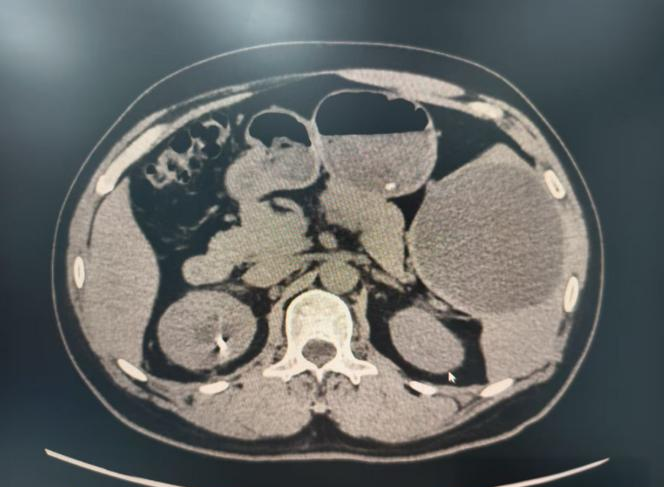

脾脏囊肿?梗死?

图片尺寸2736x3648

图片尺寸1052x794